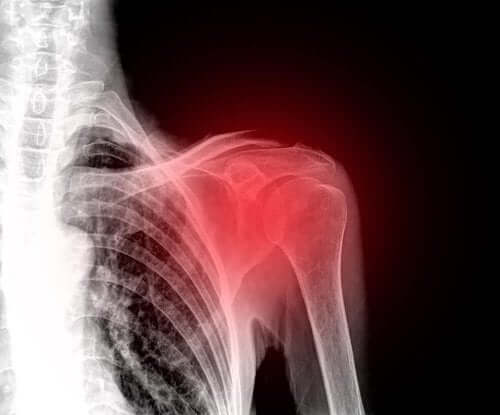

En ruptur i rotatorkappen er en skade som ofte rammer skuldrene til middelaldrende mennesker. I disse dager er det en av hovedårsakene til skuldersmerter.

Rotatorkappen er en gruppe muskler og sener som forankrer seg i skulderbeina. De er ansvarlige for å holde dette leddet stabilt slik at det kan utføre alle bevegelser riktig.

Dessverre er skulderen en kroppsdel som har en tendens til å atrofiere, noe som ofte fører til ubehag. Faktisk er en skade i dette området veldig lammende og smertefullt. Vi skal derfor forklare alt du trenger å vite om rupturer i rotatorkappen i denne artikkelen.